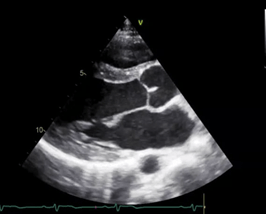

This cardiac view resembles a donut and croissant

What is the PSAX (parasternal short axis) view?

This chamber lies on top of the screen (near-field) on this cardiac view

What is the Right Ventricle?

This this apical 4 chamber view, the structures on the left side of the screen represent this side of the heart

What is the RIGHT side of the heart?